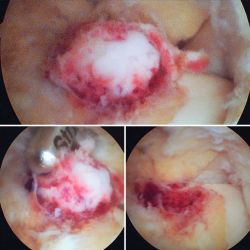

Figura 4. Mediante los portales artroscópicos anteriores habituales (anteromedial y anterolateral) se observa a nivel del cuello del astrágalo anterointerno la característica tumoración de color rojo cereza, que se desbridó con sinoviotomo.

Se visualizó la cúpula astragalina y se observó a nivel del cuello del astrágalo anterointerno una tumoración rojiza con intensa reacción sinovial; se desbridó mediante un sinoviotomo de 4,5 mm (Stryker®, Kalamazoo, Michigan) (Figura 4), tras lo cual se comprobó la inestabilidad de la lesión que se desprendió en bloque (Figura 5), remitiéndose a estudio anatomopatológico.

Figura 5. Lesión escindida en bloque, que se remite a estudio anatomopatológico.